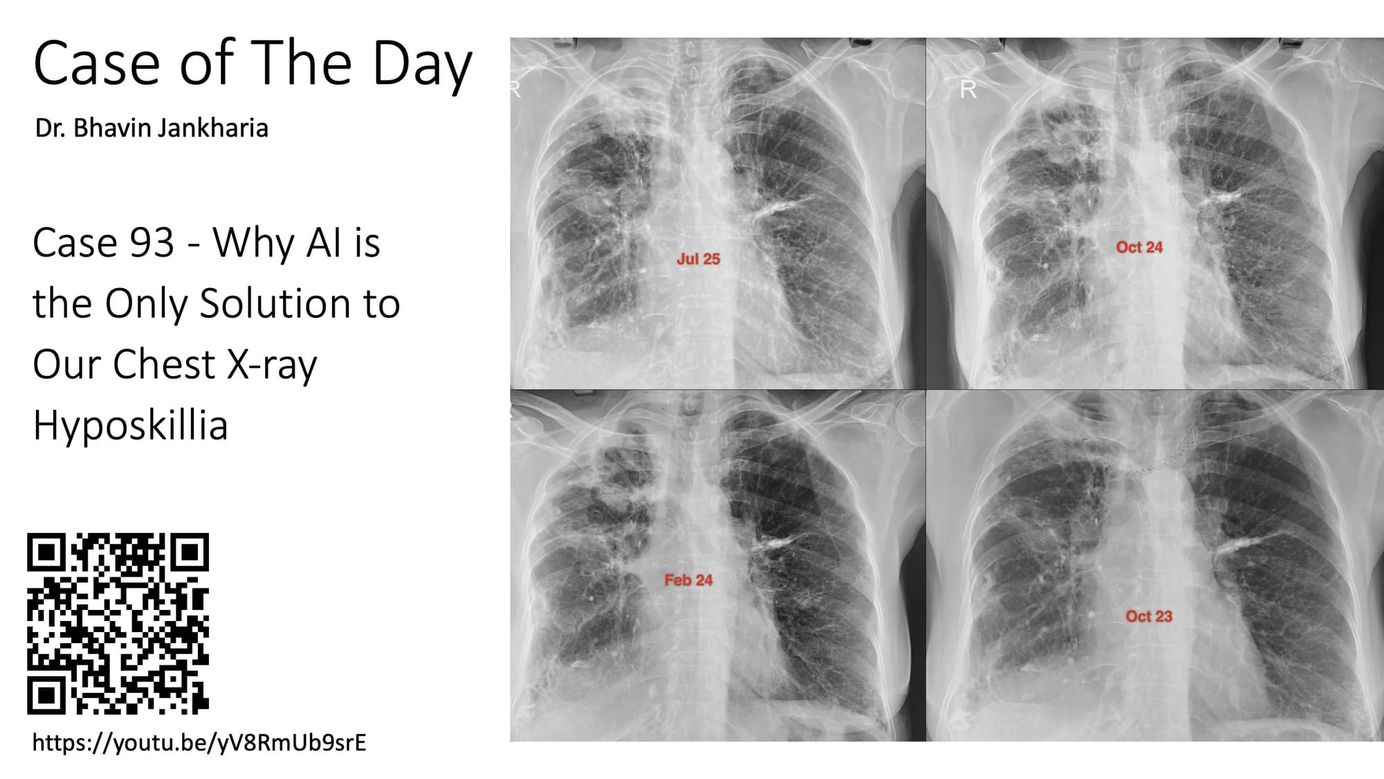

Case of the Day- 093 - 2025 08 27 - Why AI is the Only Solution to Our Chest X ray Hyposkillia Paid Members Public

A missed diagnosis for 18 months staring at us on the X-rays